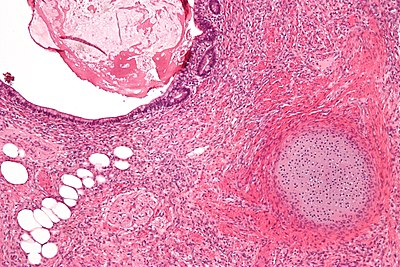

3

Diagnosis?

Teratoma intermed mag.jpg

Adenomatoid tumour

Adenocarcinoma of the rete testis

Adenomatous hyperplasia of the rete testis

Benign testis

Atrophic testis

Choriocarcinoma

Embryonal carcinoma

Immature teratoma

Infarcted testis

Inflamed testis

Germ cell neoplasia in situ

Leydig cell tumour

Lymphoma

Mature teratoma

Mixed germ cell tumour

Papillary cystadenoma of the epididymis

Seminoma

Spermatocytic tumour

Sertoli cell tumour

Sertoli cell nodule

Testicular scar

Yolk sac tumour